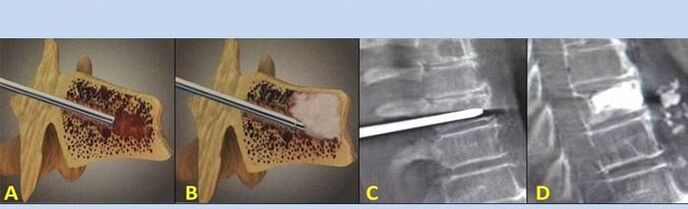

- Nucleoplasty– removal of the core of the intervertebral disc.The operation relieves pressure on the nerve endings.

- Puncture vertebroplasty– method of stabilizing the vertebrae.During the procedure, the doctor fills the cavities of the spine with bone cement.